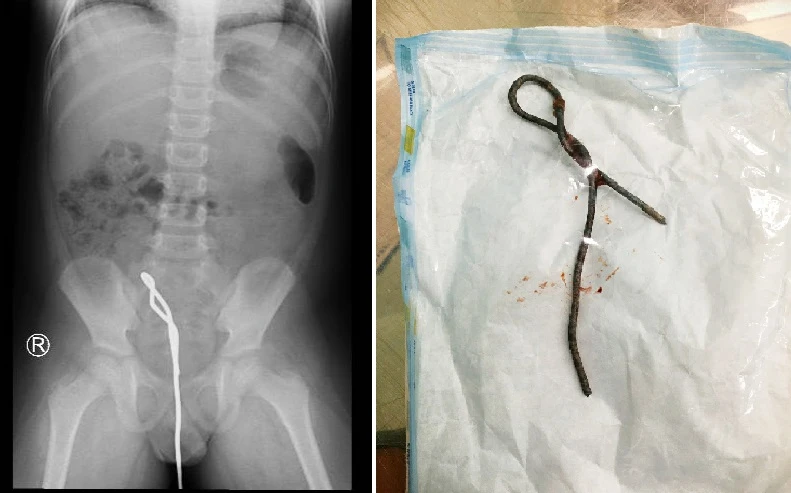

Hình ảnh cây thông cống trong cơ thể bé trai và khi được lấy ra. Ảnh: HL

Tại BV Nhi đồng Thành phố, bé được cho khẩn trương nội soi ổ bụng thám sát thấy đoạn ruột sigma bị bầm máu, chưa thấy thủng ruột. Vùng hậu môn có một cạnh sắt ghim chặt vào thành sau trực tràng.

Các bác sĩ quyết định nội soi kết hợp ngả bụng và hậu môn để lấy thanh sắt ra ngoài theo ngả hậu môn. Sau mổ, bé đang được ổn định sức khoẻ, thăm khám tâm lý, đang nhịn ăn theo dõi tiếp diễn tiến chảy máu hoặc thủng xước đường ruột.